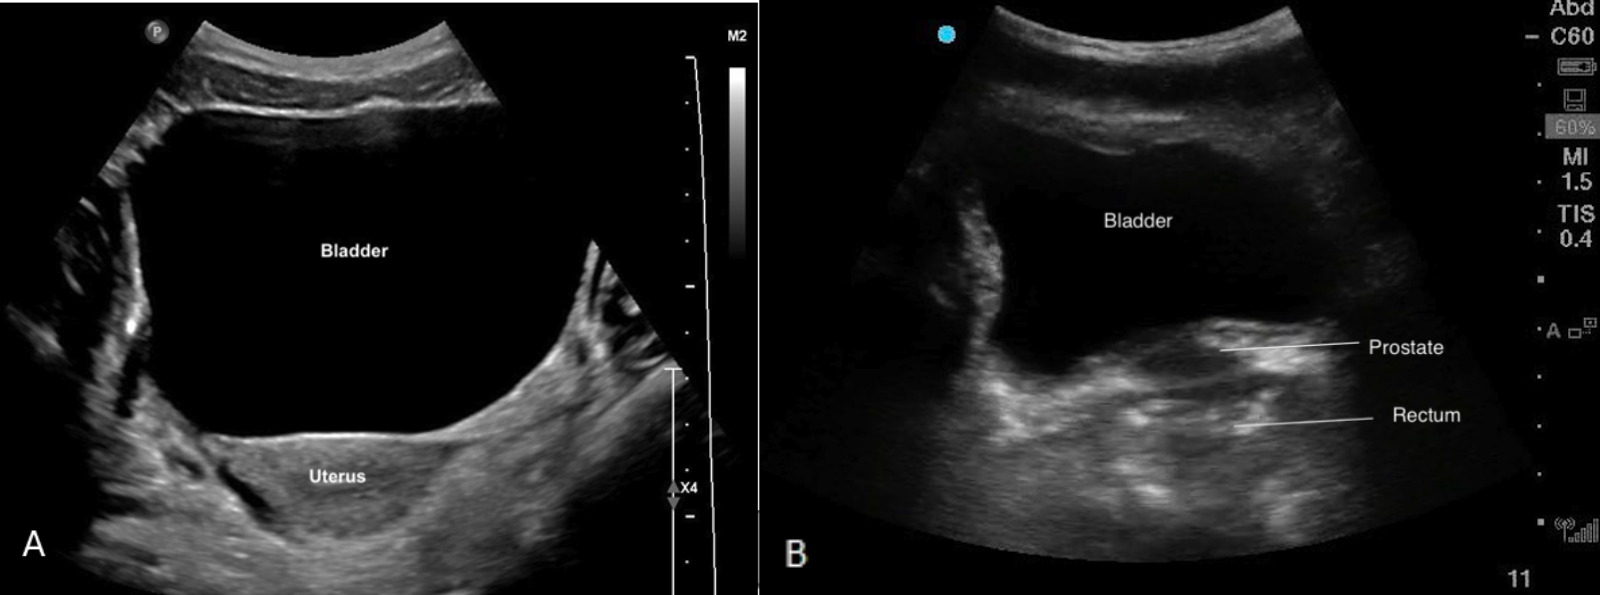

Parasternal Short Axis

Parasternal Short Axis (PSAX/PSSA)

The PSAX view provides a cross-sectional image of the ventricles, allowing simultaneous visualization of the RV and LV. For RV strain assessment, this view is useful for evaluating RV size, function. It is also the preferred view to assess the shape and position of the IVS.

The RV appears as a crescent-shaped structure anteriorly, wrapping around the circular LV cavity, with the septum forming a smooth, curved border between the two chambers (figure 8).

What is Normal?

• Crescent shaped

• Smaller than the LV

• In a normal PSAX view, the septum maintains a round, inward curvature toward the RV throughout the cardiac cycle.

Figure 7: Illustration of normal septal shape during systole and diastole in the PSAX view

Figure 8: PSAX view. Note how the septum maintains its round inward curvature during throughout the entire cardiac cycle and the crescent shape of the RV in the near field.

What is NOT Normal?

• Visually, if the RV is equal to or larger than the LV, then there is likely RV dilation. In severely dilated RVs, the LV will appear to look compressed by the RV

• Visually reduced contraction

• Septal flattening or becoming D-shaped when RV pressure > LV pressure

Septal Flattening

In the PSAX view, the LV will appear as a “D-shaped” structure. This is the result of RV volume overload (RVVO) or RV pressure overload (RVPO).

· In RVVO the septum is flattened only during diastole. This is the result of elevated RV volume filling at the expense of the LV, and causes the LV shape to deform by the end of diastole

· In RVPO the septum will be flattened throughout the entire cardiac cycle.

It is important to remember that to accurately assess septal position, the PSAX view should be obtained at the level of the papillary muscles, rather than at the mitral valve. At the mitral valve level, surrounding structures may artificially preserve septal shape despite significant RV loading.

It is also important to note that intra-cardiac shunts (e.g., VSDs) and arrhythmias can also limit the reliability of RV/LV and septal assessments in the PSAX view.

Figure 9: Illustration of Septal flattening or “D-sign” as seen in the PSAX view

Figure 10: PSAX view “D-sign” throughout cardiac cycle indicative of RVVO/RVPO